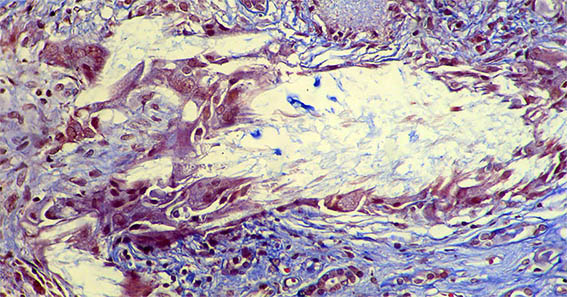

Figura 7. Tricrómico de Masson, X200.

Figura 8. Tricrómico de Masson, X400.